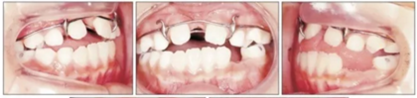

第三階段(圖7,表2)

19歲2月時行固定矯治排齊下頜牙列建立穩(wěn)定的咬合及正常的覆合覆蓋,持續(xù)1年10月。摘除后(21歲)上下頜用固定保持器,上頜牙弓用Hawley保持器。